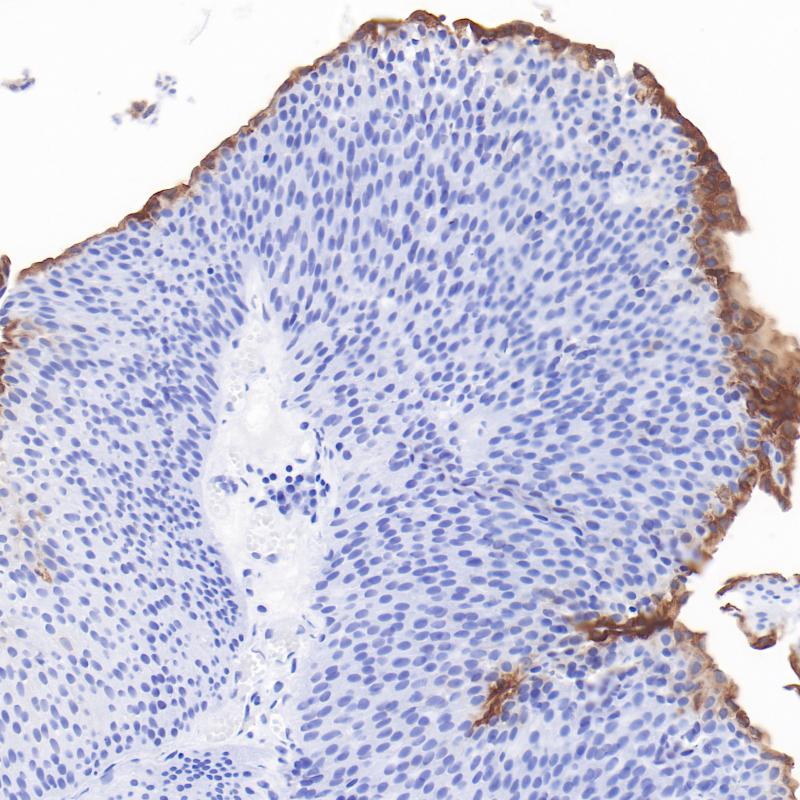

雌激素受体(ER)属于核受体超家族的类固醇受体,由553个氨基酸组成。雌激素受体分子具有三个结构域,即DNA结合中央结构域,C末端的激素结合结构域和N末端的转录激活结构域。ER参与女性性激素的调节功能,主要是17(E2),在一些目标组织的生长、分化和功能方面,如女性和男性生殖道,乳腺,骨骼和心血管系统。ER α存在于正常乳腺和子宫内膜组织的上皮细胞的细胞核,以及乳腺癌的亚型中。其次, ER α可作为一个肿瘤标志物,与抗孕酮受体的抗体组合,可用于腺癌的分类。

阳性对照

乳腺癌

亚细胞定位

细胞核